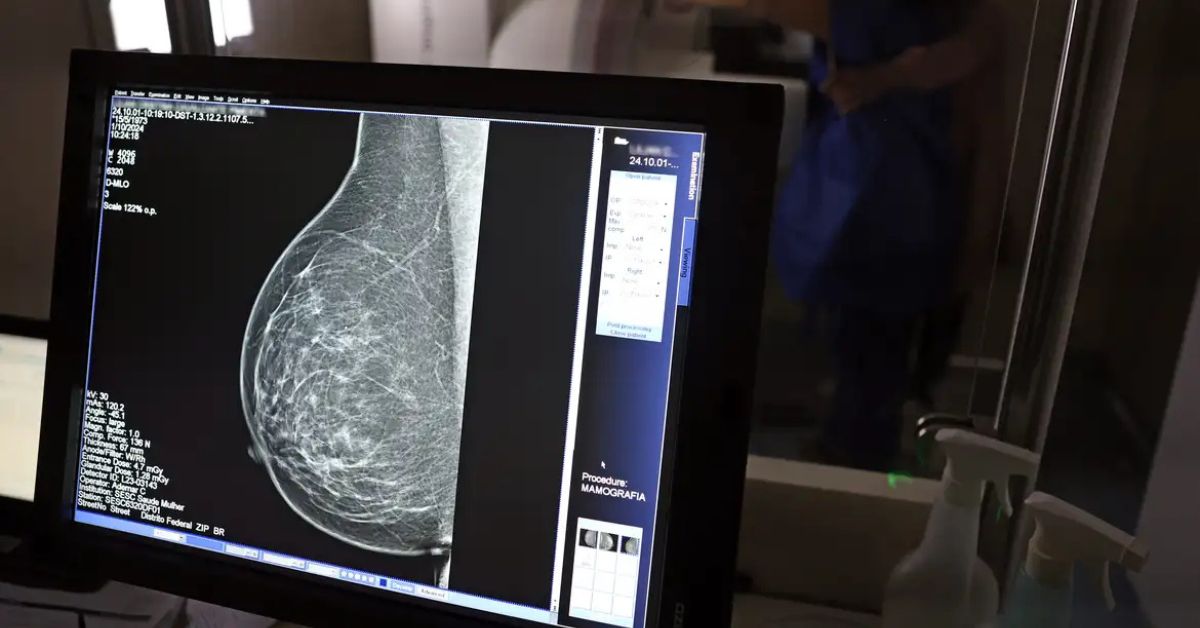

Exame de mamografia realizado com direito à folga para exames preventivos garantida por lei

Lei garante até três dias de folga para exames preventivos, facilitando o diagnóstico precoce. (Foto: José Cruz/Agência Brasil)